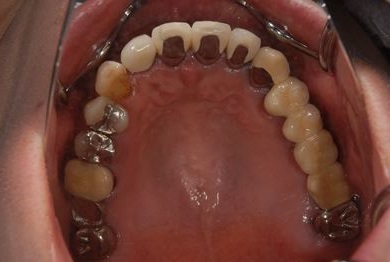

| 性別/年齢 | 女性 / 44歳 | ||||||||||||||||||||||||||||||||

| 主訴 | 上のさし歯がグラグラする。インプラントにした方が良いのか、相談したい。 | ||||||||||||||||||||||||||||||||

| 治療方針 | 抜歯と同時にインプラントを埋入し、治療期間を短縮する。 | ||||||||||||||||||||||||||||||||

| 治療内容 | インプラント2本(抜歯即日スピードインプラント)、メタルボンドセラミック2本 | ||||||||||||||||||||||||||||||||